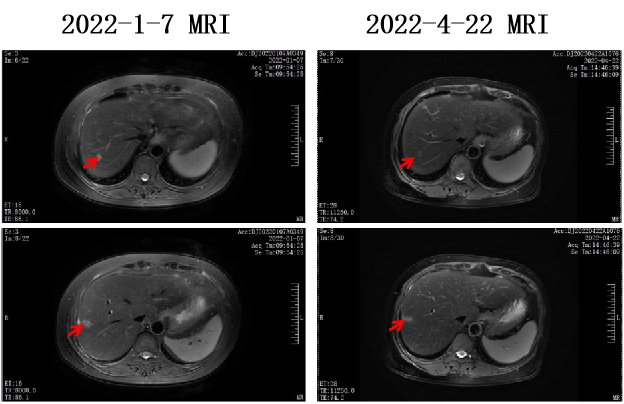

2022-1-8至2022-5-20 共行6周期 贝伐珠单抗+伊立替康+奥沙利铂+卡培他滨方案化疗。

术后5周期化疗后复查疗效为SD。

2022-6-22 开始行贝伐珠单抗+卡培他滨维持治疗。

该病例虽然肿瘤负荷大,采用贝伐珠单抗联合三药化疗的方案,显示了原发病灶和肝内转移灶、淋巴结转移灶都获得了明显的控制,部分病灶达到CR,为手术切除创造了良好的机会。因此,对于体力状况好的晚期结直肠癌患者,三药治疗有更好的转化效率;同时,抗血管生成治疗应在更多的晚期结直肠癌病例中推广使用,以使更多的患者能够获得持久的肿瘤缓解。